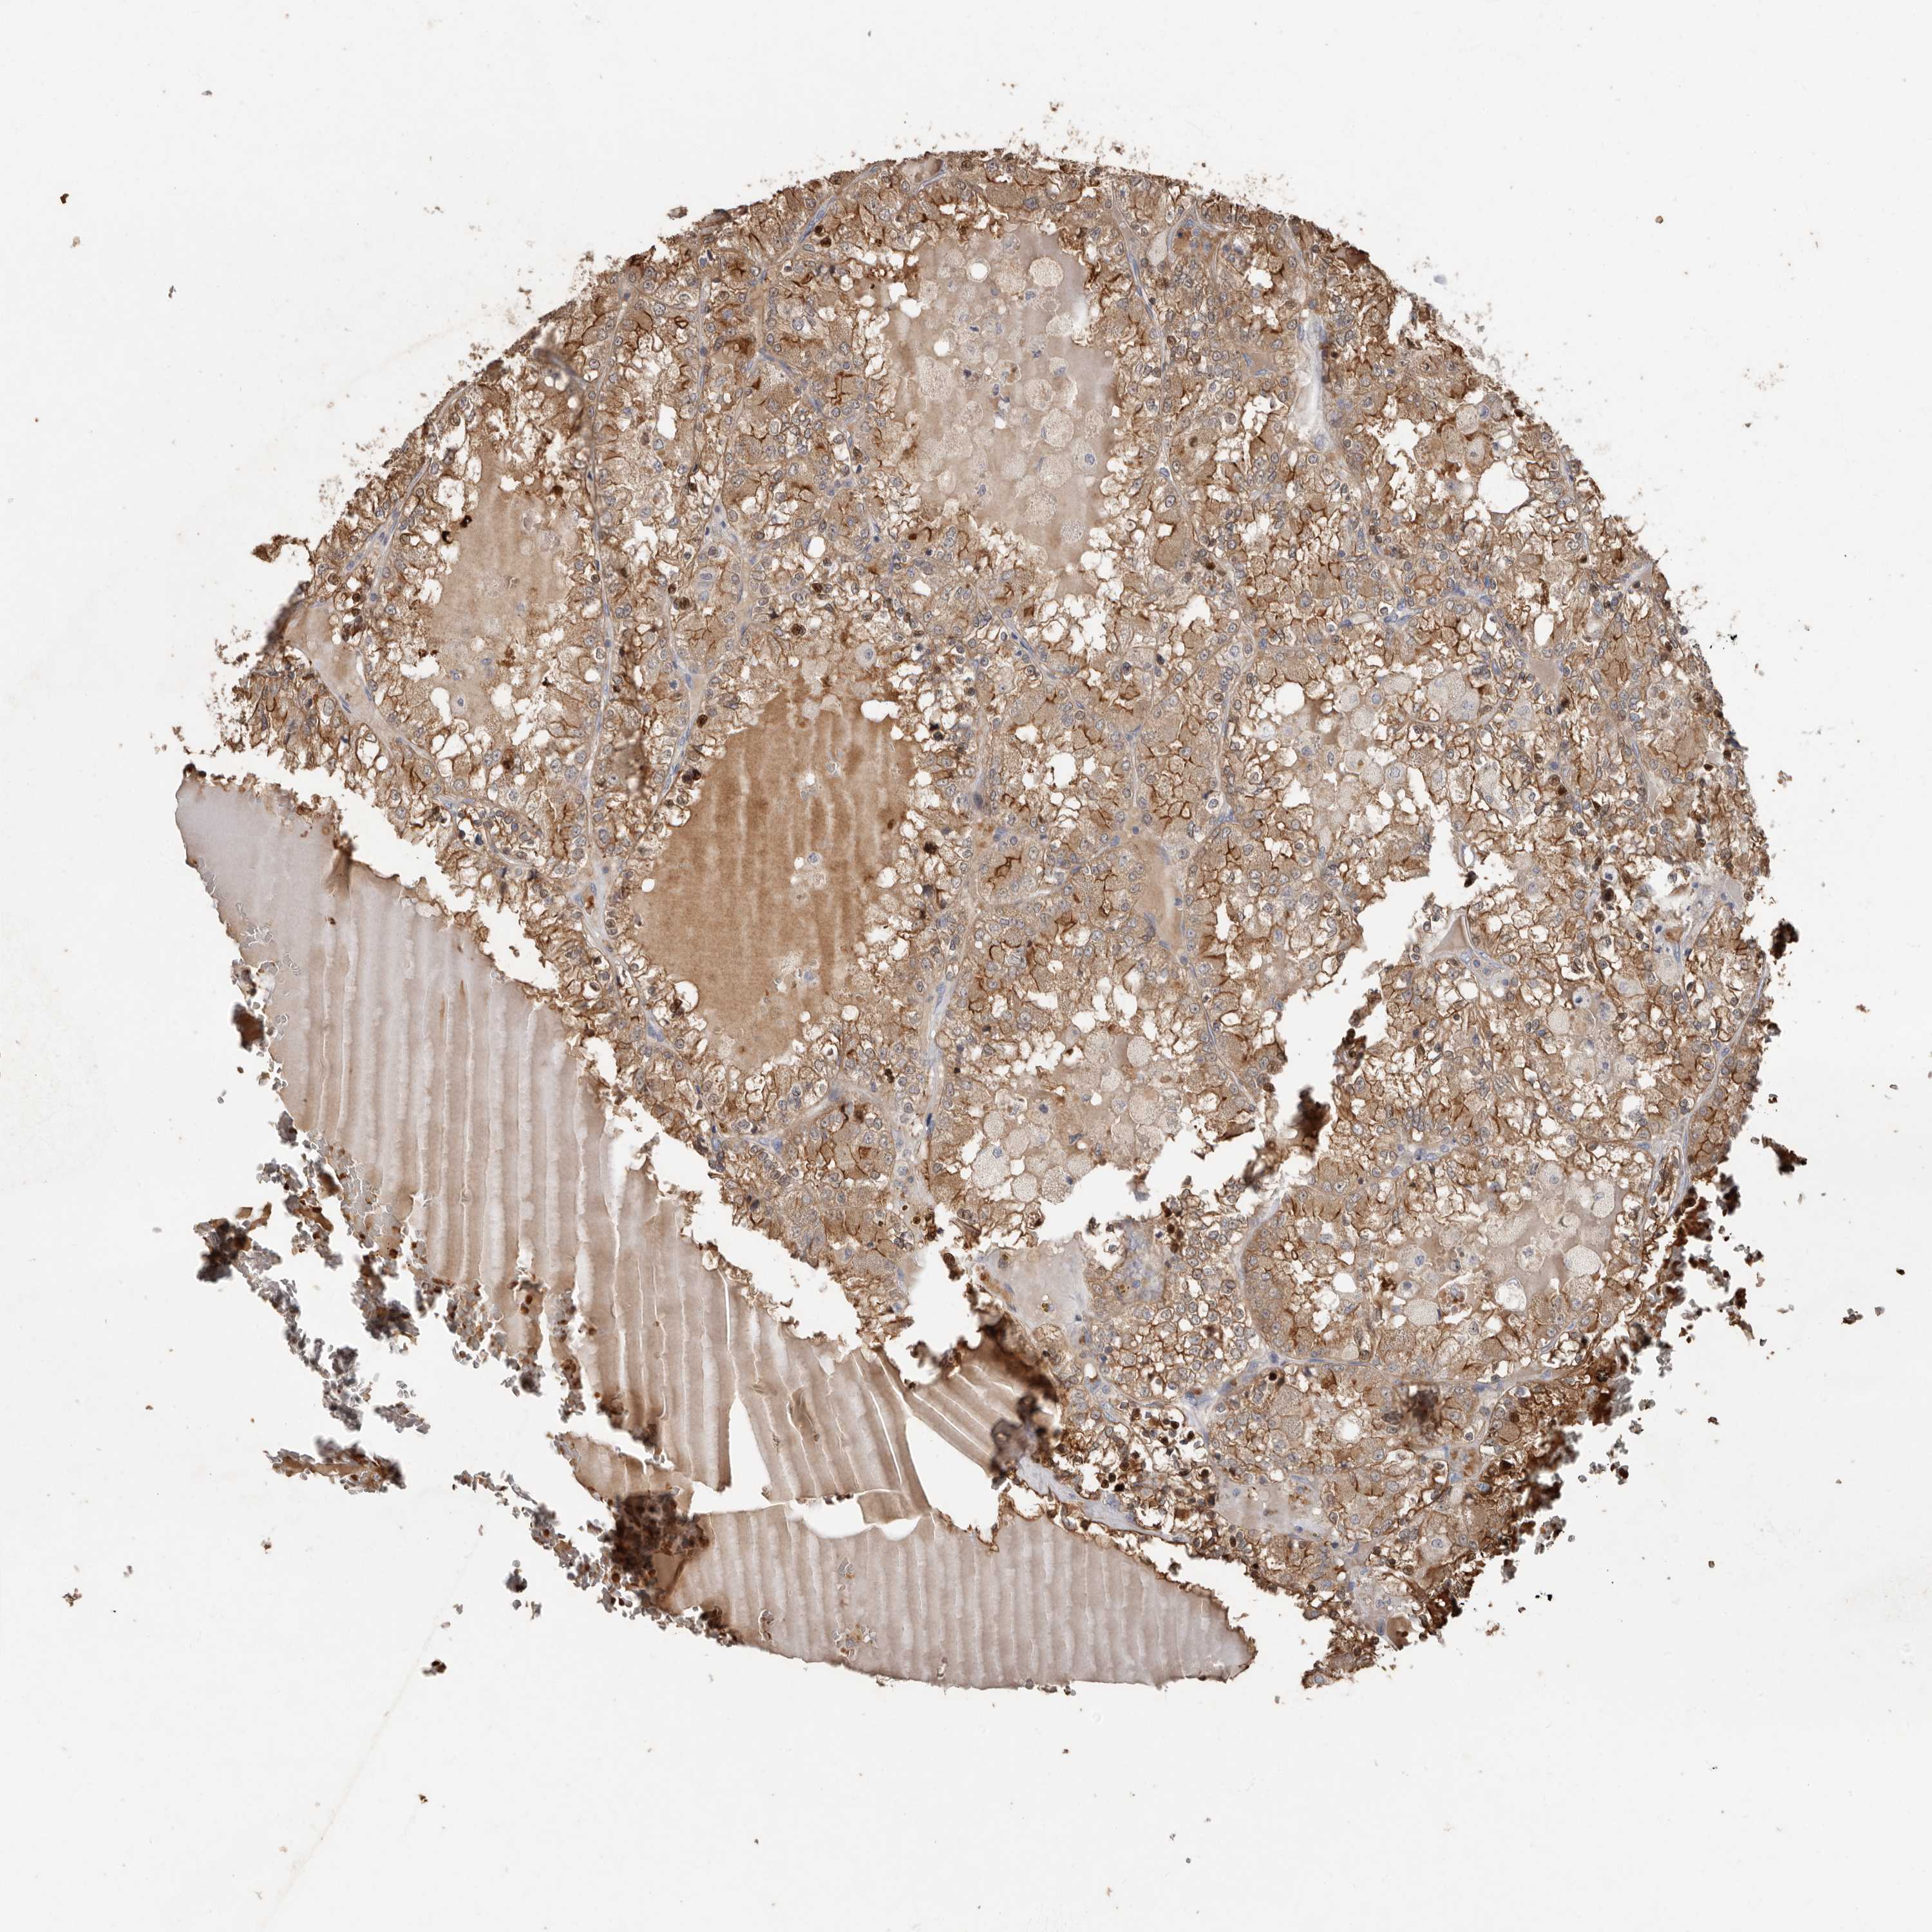

CANCER RENAL CANCER Show tissue menu

KICH TCGA KIRC TCGA KIRC VALIDATION KIRP TCGA PROTEIN RCC CPTAC PROTEIN EXPRESSION